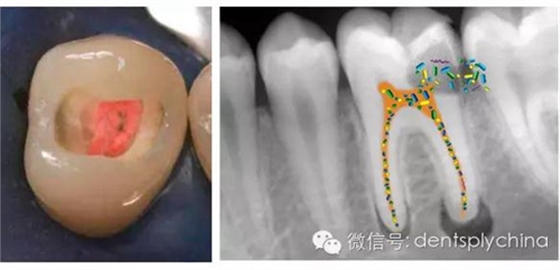

根管治療-消除根尖周感染

根管治療后牙齒的根尖周狀態(tài)和根管充填和冠部修復(fù)的關(guān)系

超低收縮應(yīng)力、4mm一層充填的SDR可以極大的改善冠部封閉

使用SDR作為冠部封閉